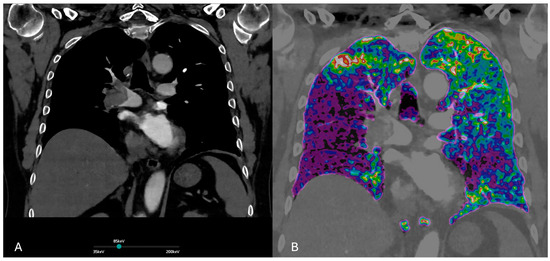

3.2. Dual Energy CT

3.2.1. Principles of DECT

3.2.2. Accuracy of DECT